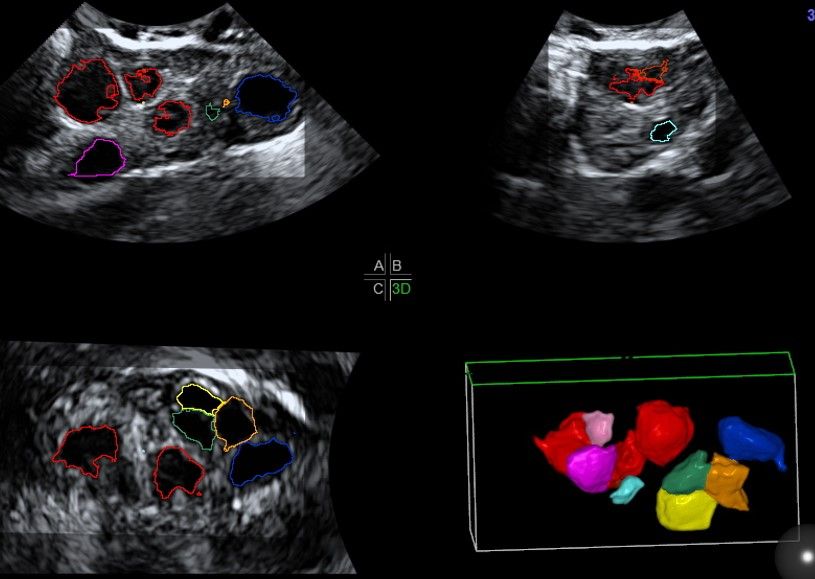

Современные экспертные УЗИ сканеры дают возможность проводить исследования всех органов в 3D. Это позволяет, используя полученный массив данных, получать диагностические сечения в любой плоскости, недоступной для обычного 2D УЗИ. Наиболее интересной является фронтальная. Например, визуализация полости матки. Диагностическая возможность выявления пороков развития превосходит все другие методы (рентгеновские и МРТ). Метод также позволяет уточнить положение ВМК (спирали) в полости матки, расположение миоматозных узлов, расположение плодного яйца на малых сроках, полипов. Сегодня современное экспертное ультразвуковое исследование невозможно без использования 3D УЗИ.